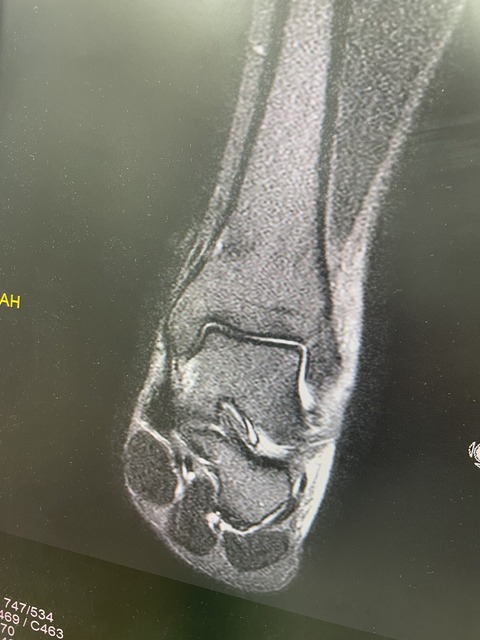

2025年10月04日 一般患者様みながら、連日アスリート 全日本モトクロス選手権、チャンピオン 残り2戦 何とか怪我に負けずに 入賞させよう、 今年は5連覇がかかっておりますので どうしても直していきたいと思います プロキックボクサー 回し蹴りで、骨折 フレックスサインあるも これは保存的治療で直します . カテゴリなしの他の記事 < 前の記事次の記事 >